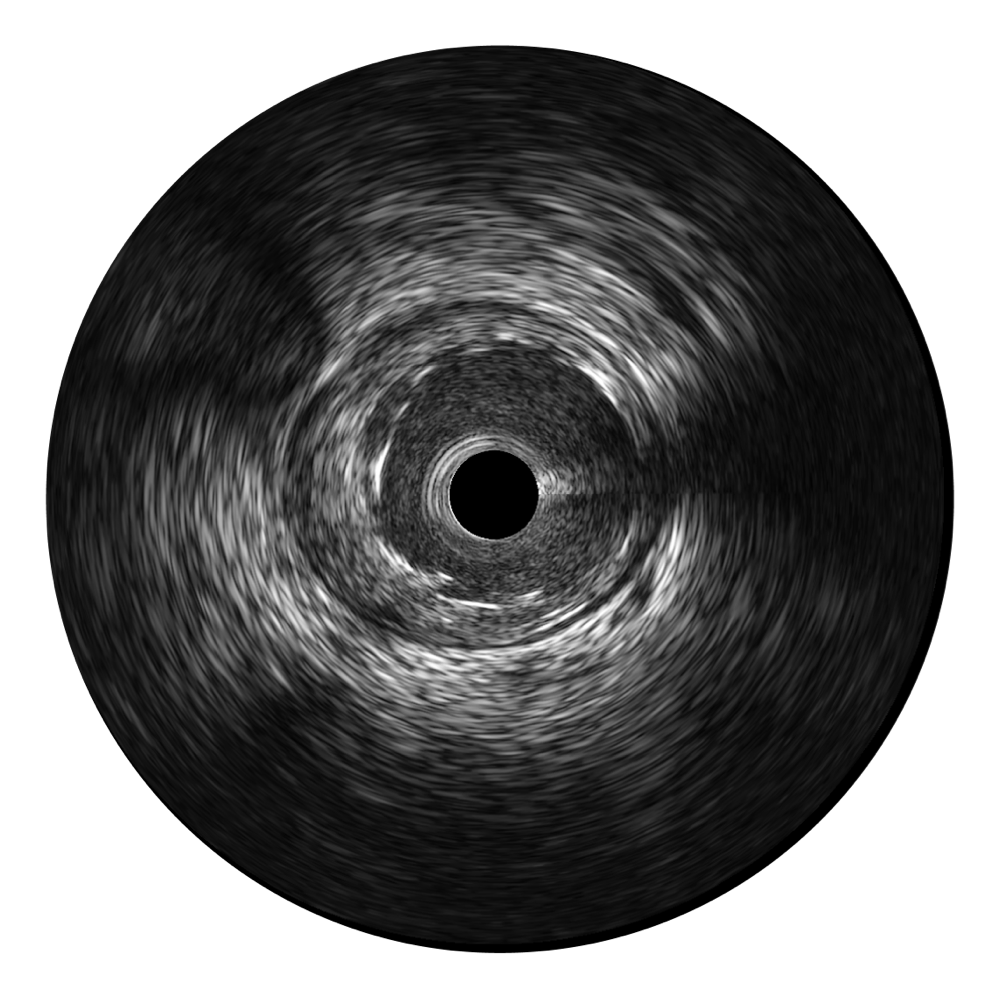

传统IVUS图像

对比传统IVUS导管成像,百老汇电子游戏官网宽频IVUS图像的近场支架梁显影更细腻,远场中膜外血管仍清晰可辨,兼顾远中近,兼顾分辨力与穿透深度